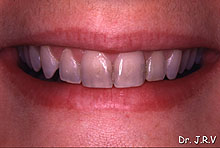

| Fotos 2A y 2B.- Imágenes de la sonrisa de una paciente

cuyos dientes presentan una tinción por tetraciclinas. |

Estos

casos pueden tratarse directamente con composites o con carillas de porcelana7.

La elección de uno u otro dependerá de la habilidad del operador

y de la dificultad de la restauración, aunque en muchas ocasiones y,

debido a la aparición de diferentes opacificadores, las restauraciones

directas con composites son una alternativa terapéutica que permite

obtener resultados estéticos muy satisfactorios8.